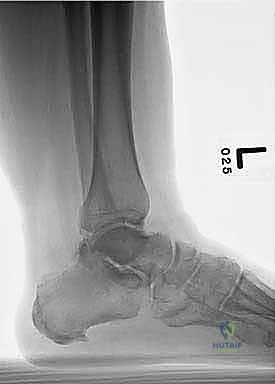

Walks with a severe limp and has failed bracing, including patellar-tendon bearing brace ( TECH FIG 7A )

- Initial review of AP and lateral radiographs suggests that talar anatomy is relatively well preserved; however, closer inspection of AP radiograph demonstrates some potential lucency/irregularity in

D E talar body, and lateral radiograph reveals some talar body collapse and subtalar incongruity ( TECH FIG 7B,C ).

TECH FIG 7 • A. Patellar tendon bearing brace. B, C. Preoperative radiographs of patient with talar body avascular necrosis. D, E. CT scan of same patient in A . Note fatigue fractures in the talar body.